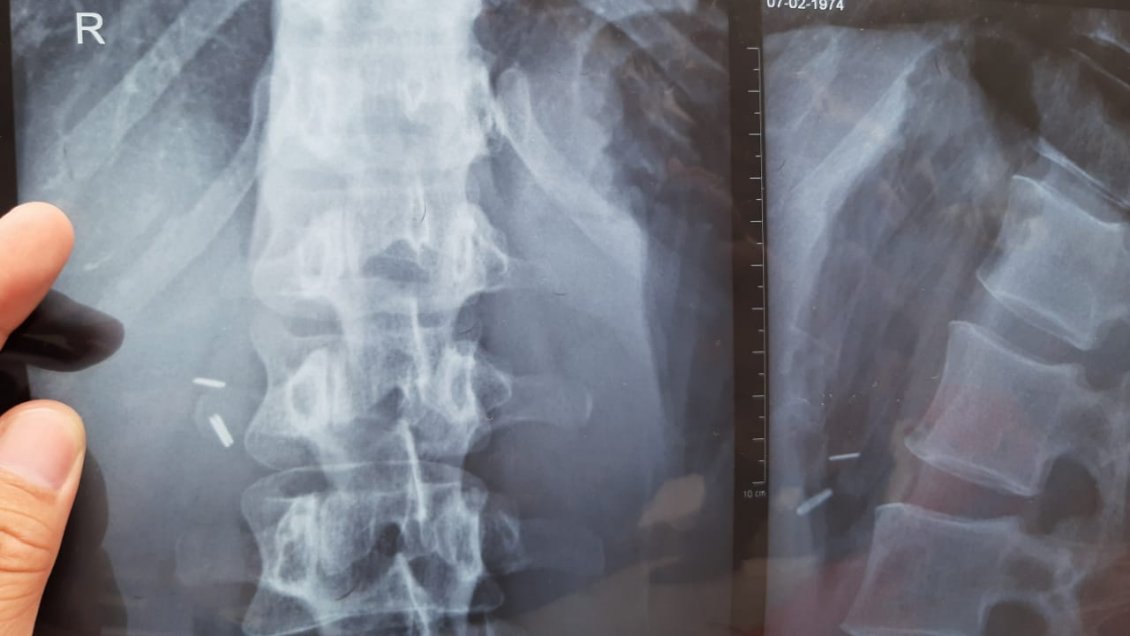

María Ivonne Sandoval, de 48 años, acusó que tras realizarse una colectomía -operación que consiste en la extirpación de una parte enferma del intestino grueso- tres corchetes quedaron al interior de su cuerpo, lo que fue dañando su salud ya que estos elementos avanzaron hacia el pulmón y cercano al corazón.

La afectada relató que "fui operada en el 2014 de una colectomía que me hicieron acá. Hace poco tiempo atrás a un doctor le conté lo que me estaba sucediendo y me dijo que me tenía que sacar una radiografía urgente para ver la patología que podía tener y en eso nos llevamos la tremenda sorpresa que me habían dejado corchetes dentro de mi cuerpo".

El facultativo explicó que "cuando ocurre algo así, primero, se instruye una investigación, porque viendo las imágenes radiográficas, no es claro de que tengan relación con esa cirugía esos corchetes".

Donoso explicó que "están en una zona que si se hubiera hecho la operación que dice es muy difícil que lleguen a esa zona, por lo tanto, esto tiene que ser investigado, tiene que ver qué se usó en esa operación, si corresponde y, por último, un corchete dentro del cuerpo no necesariamente significa un problema".